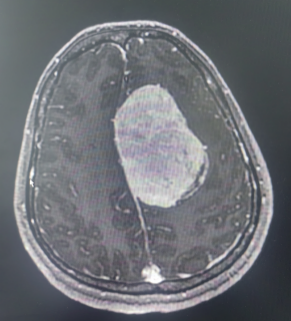

患者系中年女性,因出现偏侧肢体活动不灵和头痛症状,经检查发现颅内大脑镰旁长有一直径7cm的巨大肿瘤。肿瘤位于大脑的运动功能区,血供丰富,这一区域的手术风险极大。在决定手术治疗之前,神经外科医生与患者家属进行了充分的沟通,详细解释了手术的必要性、可能的风险和并发症,包括出血、感染、血管和神经损伤以及脑功能障碍等。家属在充分了解情况后,同意进行手术。面对这一复杂病例,我院迅速组织了由神经外科、麻醉科、心内科、输血科等多个科室的专家团队进行会诊,共同制定了先介入栓塞,再手术切除的治疗方案。

神经外科血管介入组曲友直副教授、崔刚副教授和高攀主治医师对肿瘤进行了瘤栓塞治疗,有效减少了肿瘤的血供,为后续的手术切除降低了风险。栓塞治疗后,神经外科王睿智副主任、高李贵副教授和董全主治医师在麻醉科、心内科、输血科等科室的全力配合下,凭借精湛的医术和丰富的临床经验,成功为患者切除了病变。手术过程中,麻醉科吕建瑞主任团队全程监控患者的生命体征,确保麻醉安全;心内科团队随时准备应对可能出现的心脏问题;输血科团队则确保充足的血液供应,以备不时之需。多学科的通力合作,为手术的成功提供了坚实的保障。